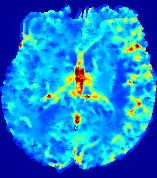

LesionRefer to captionRefer to captionRefer to captionRefer to captionRefer to captionRefer to caption𝐕rgbsubscript𝐕𝑟𝑔𝑏{\bf{V}}_{rgb}Refer to captionRefer to captionRefer to captionRefer to captionRefer to captionRefer to caption𝐕2subscriptnorm𝐕2{\|\bf{V}}\|_{2}Refer to captionRefer to captionRefer to captionRefer to captionRefer to captionRefer to captionRefer to caption3.53.53.52.82.82.82.12.12.11.41.41.40.70.70.70.00.00.0(mm/s)𝑚𝑚𝑠(mm/s)D𝐷DRefer to captionRefer to captionRefer to captionRefer to captionRefer to captionRefer to captionRefer to caption0.0200.0200.0200.0160.0160.0160.0120.0120.0120.0080.0080.0080.0040.0040.0040.0000.0000.000(mm2/s)𝑚superscript𝑚2𝑠(mm^{2}/s)Slice #1Slice #2Slice #3Slice #4Slice #5Slice #6

Figure 4: PIANO feature maps for another patient in the ISLES 2017 training set, where the lesion is located in the right hemisphere. Top row: segmented stroke lesion region (white) on different slices. The corresponding slices for the PIANO feature maps are shown in the following rows.

For a better insight into an estimated velocity field 𝐕𝐕{\bf{V}} and diffusion field 𝐃𝐃{\bf{D}}, we compute the following maps: (1) 𝐕rgbsubscript𝐕𝑟𝑔𝑏{\bf{V}}_{rgb}: Color-coded orientation map of 𝐕=(Vx,Vy,Vz)T𝐕superscriptsuperscript𝑉𝑥superscript𝑉𝑦superscript𝑉𝑧𝑇{\bf{V}}=(V^{x},V^{y},V^{z})^{T}, obtained by normalizing 𝐕𝐕{\bf{V}} to unit length and mapping its 3 components to red, green, blue respectively; (2) 𝐕2subscriptnorm𝐕2\|{\bf{V}}\|_{2}: 222 norm of 𝐕𝐕{\bf{V}}; (3) D𝐷D: scalar field in Eq. 5.

Fig. 3 and Fig. 4 show the PIANO feature maps estimated from two ISLES 2017 patients: all are highly consistent with the lesion in both cases. Details of the blood flow trajectories are revealed in 𝐕rgbsubscript𝐕𝑟𝑔𝑏{\bf{V}}_{rgb} by the ridged patterns and the sharp changes of colors in the unaffected (right) hemisphere, while the flat patterns appearing within the lesion provide little directional information about the velocity and indicate low velocity magnitudes. Velocity magnitudes are more directly visualized via 𝐕2subscriptnorm𝐕2\|{\bf{V}}\|_{2}, from which one can easily locate the lesion where 𝐕2subscriptnorm𝐕2\|{\bf{V}}\|_{2} is low. D𝐷D also indicates lower diffusion values in the lesion, though with less contrast potentially due to the fact that it captures the accumulated effect of CA diffusion at the voxel-level.